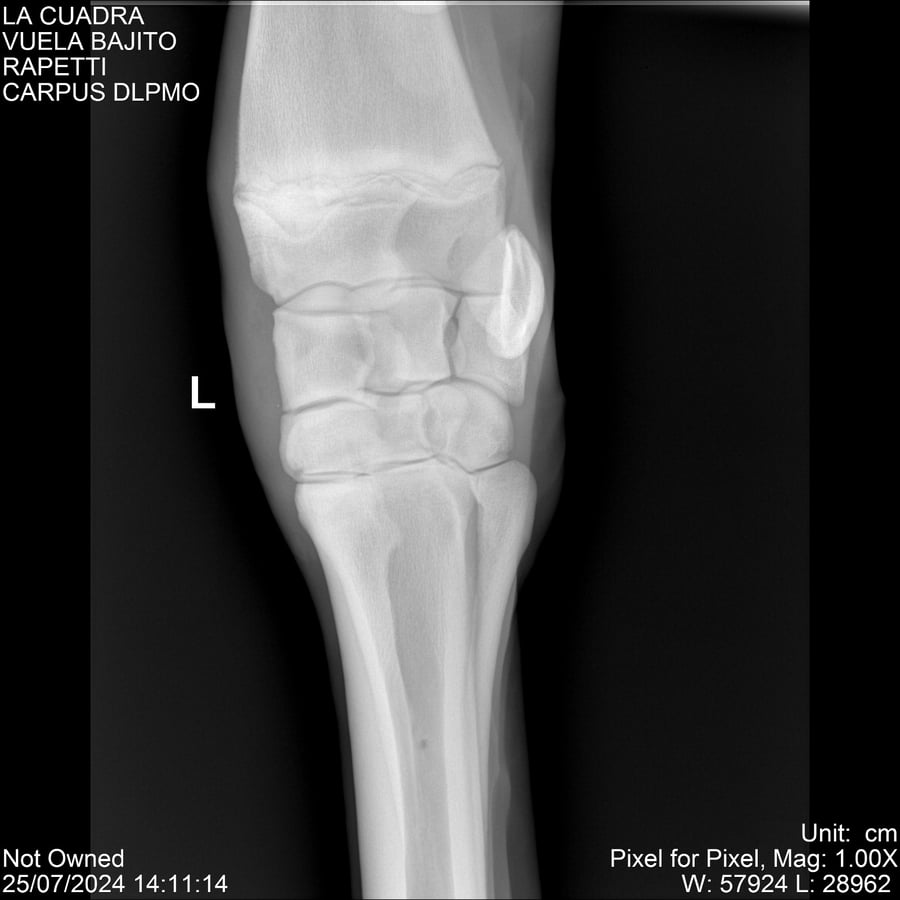

LOTE 16, VUELA BAJITO Lote Anterior Volver al remate Lote Siguiente Ficha Contacto Montevideo - Ficha del Lote Identificador: #284451 Categoría: Yeguarizos Montevideo - 77 Visualizaciones ClicData Contacto Empresa: Abelenda N. R., Walter Hugo Nombre*: Teléfono* : E-mail* : Mensaje Enviar Registrese gratis Este contenido Exclusivo está disponible sólo para usuarios registrados Ingresar